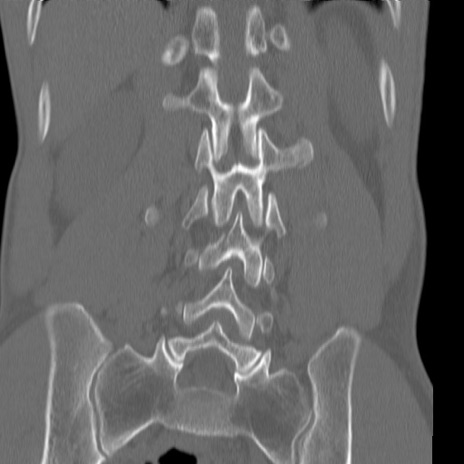

症例3 腰椎CT(冠状断像)

腰椎CT

3D再構成